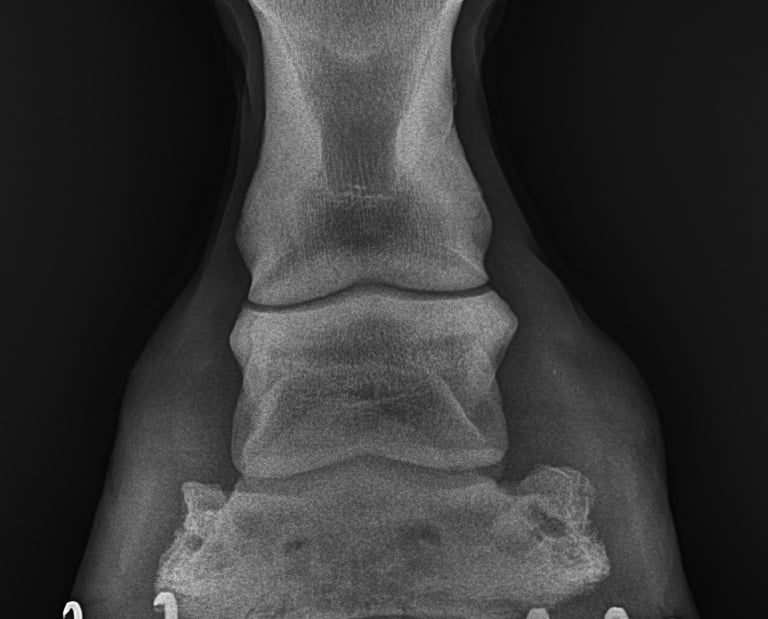

Te guiare paso a paso para desarrollarte en la clinica equina y en el diagnostico de patologias osteoarticulares, tendinosas y ligamentosas del aparato locomotor equino

DIAGNOSTICO POR IMAGENES: ECOGRAFIA Y RADIOGRAFIA